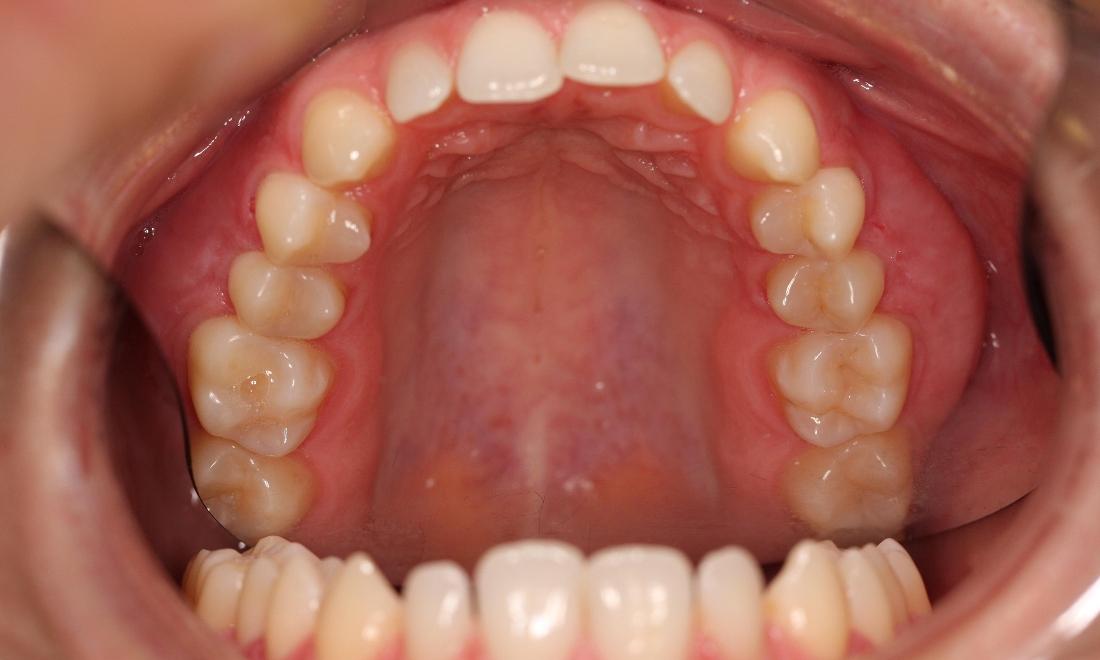

This young woman was self conscious about the crowding in her upper and lower teeth. After months of invisalign treatment, she is very satisfied with the result.